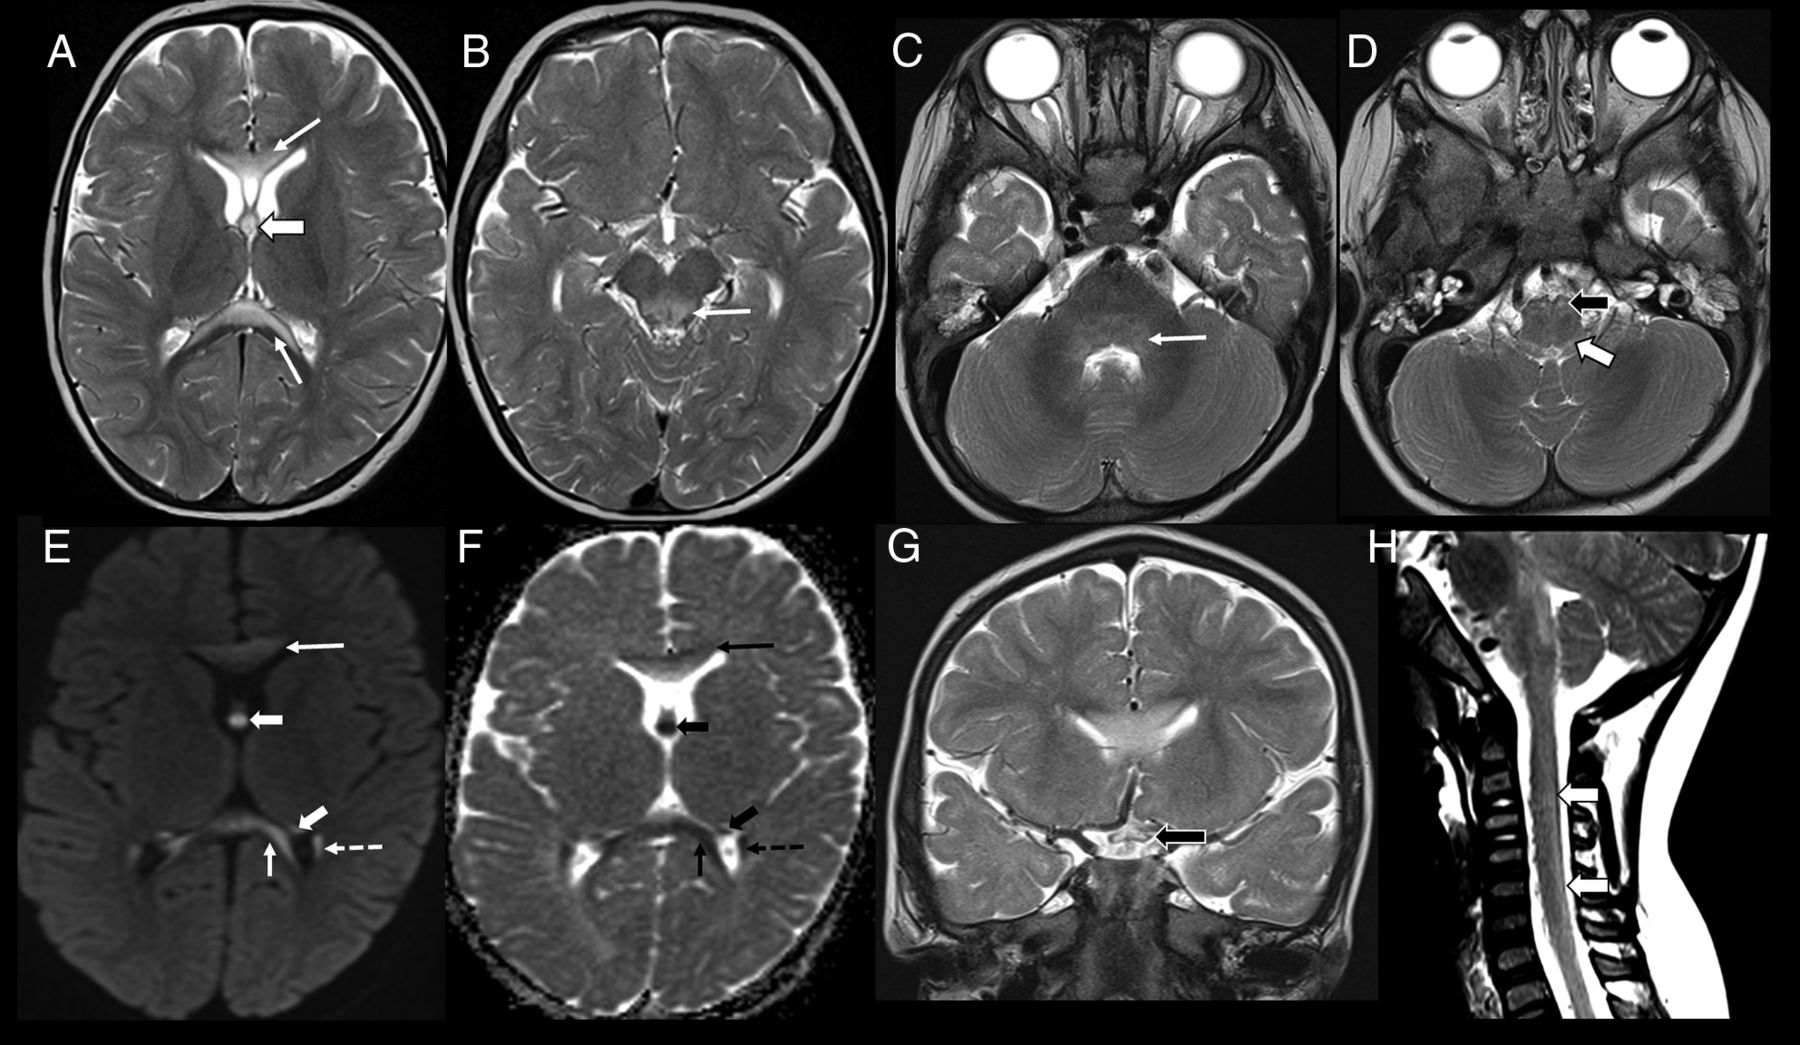

Imaging appearance in the early childhood age group (patient 8, 18 months of age). Axial T2-weighted images show hyperintense lesions involving the genu and splenium of corpus callosum (A, arrows), forniceal columns (A, arrowhead); dorsal midbrain including the periaqueductal gray matter (B, arrow); dorsal pons (C, arrow), medullary pyramids (D, black arrowhead), and dorsal medulla (D, white arrowhead). Axial DWI (E) and ADC (F) images show restricted diffusion involving the corpus callosum (arrows), fornices (arrowheads), and tapetum (dashed arrow). Coronal T2-weighted image (G) shows involvement of the optic chiasm (black arrowhead). Sagittal T2-weighted image of the cervical spine (H) shows faint hyperintensity involving the dorsal cervical cord (white arrowheads).

All 3 patients showed signal abnormalities in the fornices (confined only to the body in patient 2), periaqueductal gray matter, dorsal pons, and medullary pyramids. Two patients (patients 6 and 8) also had signal abnormalities in the superior and inferior colliculi; superior, middle, and inferior cerebellar peduncles; corpus callosum (inner blade of genu in patient 6, middle blade of the entire corpus callosum in patient 8); prechiasmatic optic nerves and optic chiasm; and cervical spinal cord (lateral columns in patient 6, dorsal columns in patient 8). Patient 2 also showed signal abnormalities in the medial thalami, whereas patient 6 also showed involvement of the lateral geniculate bodies, hippocampal formations, parahippocampal gyri, mamillary bodies, and hypothalamus. Imaging findings in patient 8 are depicted in Fig 3.

All patients were treated with biotin (10 mg in patients 2 and 8 and 15 mg in patient 6). Follow-up imaging was not available for any patient. On clinical follow-up, patients 2 and 8 recovered completely with no residual deficits, whereas patient 6 had bilateral optic atrophy and bilateral moderate sensorineural hearing loss.